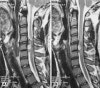

MRI : Low signal in T1, High signal in T2

MRI : 유골골종(Osteoid osteoma) & 골아세포종(Osteoblastoma)